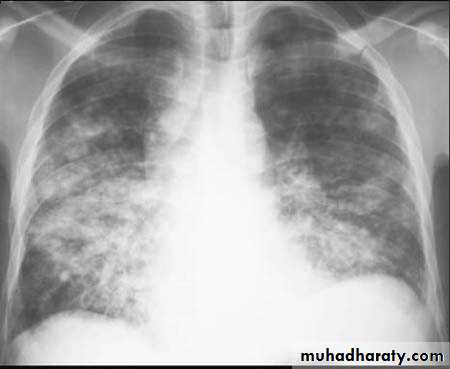

Chest X-ray shows mottled opacities in both lung fields, chiefly in the lower zones (Bronchopneumonia).